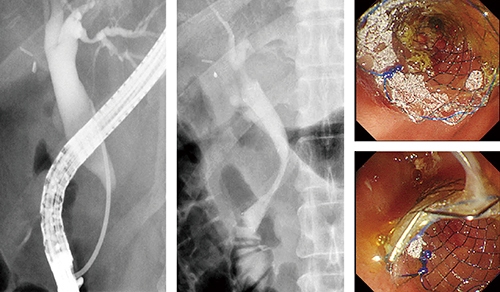

症例1は、膵頭部がんに対し化学療法を施行した症例である。術前に金属ステントを留置したが、黄疸が悪化したため、Duckbill型逆流防止弁付き金属ステントに変更した。Duckbill型逆流防止弁付き金属ステントは、内視鏡下ではマーカーが見えにくいため、透視下で十二指腸下行脚部を確認しつつ問題なく留置することができた(図5)。

図5 症例1:膵頭部がん(62歳、女性)

Duckbill留置

パルスレート7.5fps、線量モード:Normal